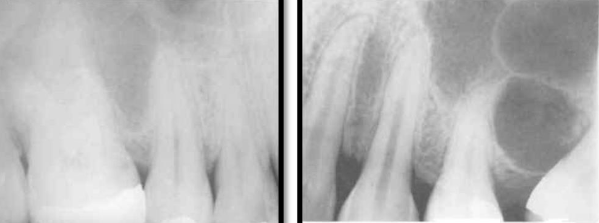

mandibular canal

aka: inferior dental canal

runs from the mandibular foramen in the ramus to the mental foramen

seen as a radiolucent band and may lie in close association with the apices of molar and 2nd premolar teeth

mental foramen

located below and distal to the apex of the 1st premolar

may be mistaken for a pathological lesion when it appears close to the apex of one of the premolars, which is due to the angle at which the radiograph is taken